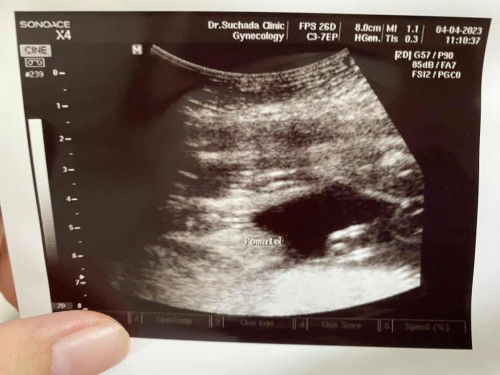

ชัวร์ค่ะ แม่เห็นสีขาวเข้มสามกลีบนั้นมั้ยคะ เห็นชัดเจนแบบนี้ ลูกสาว 100%